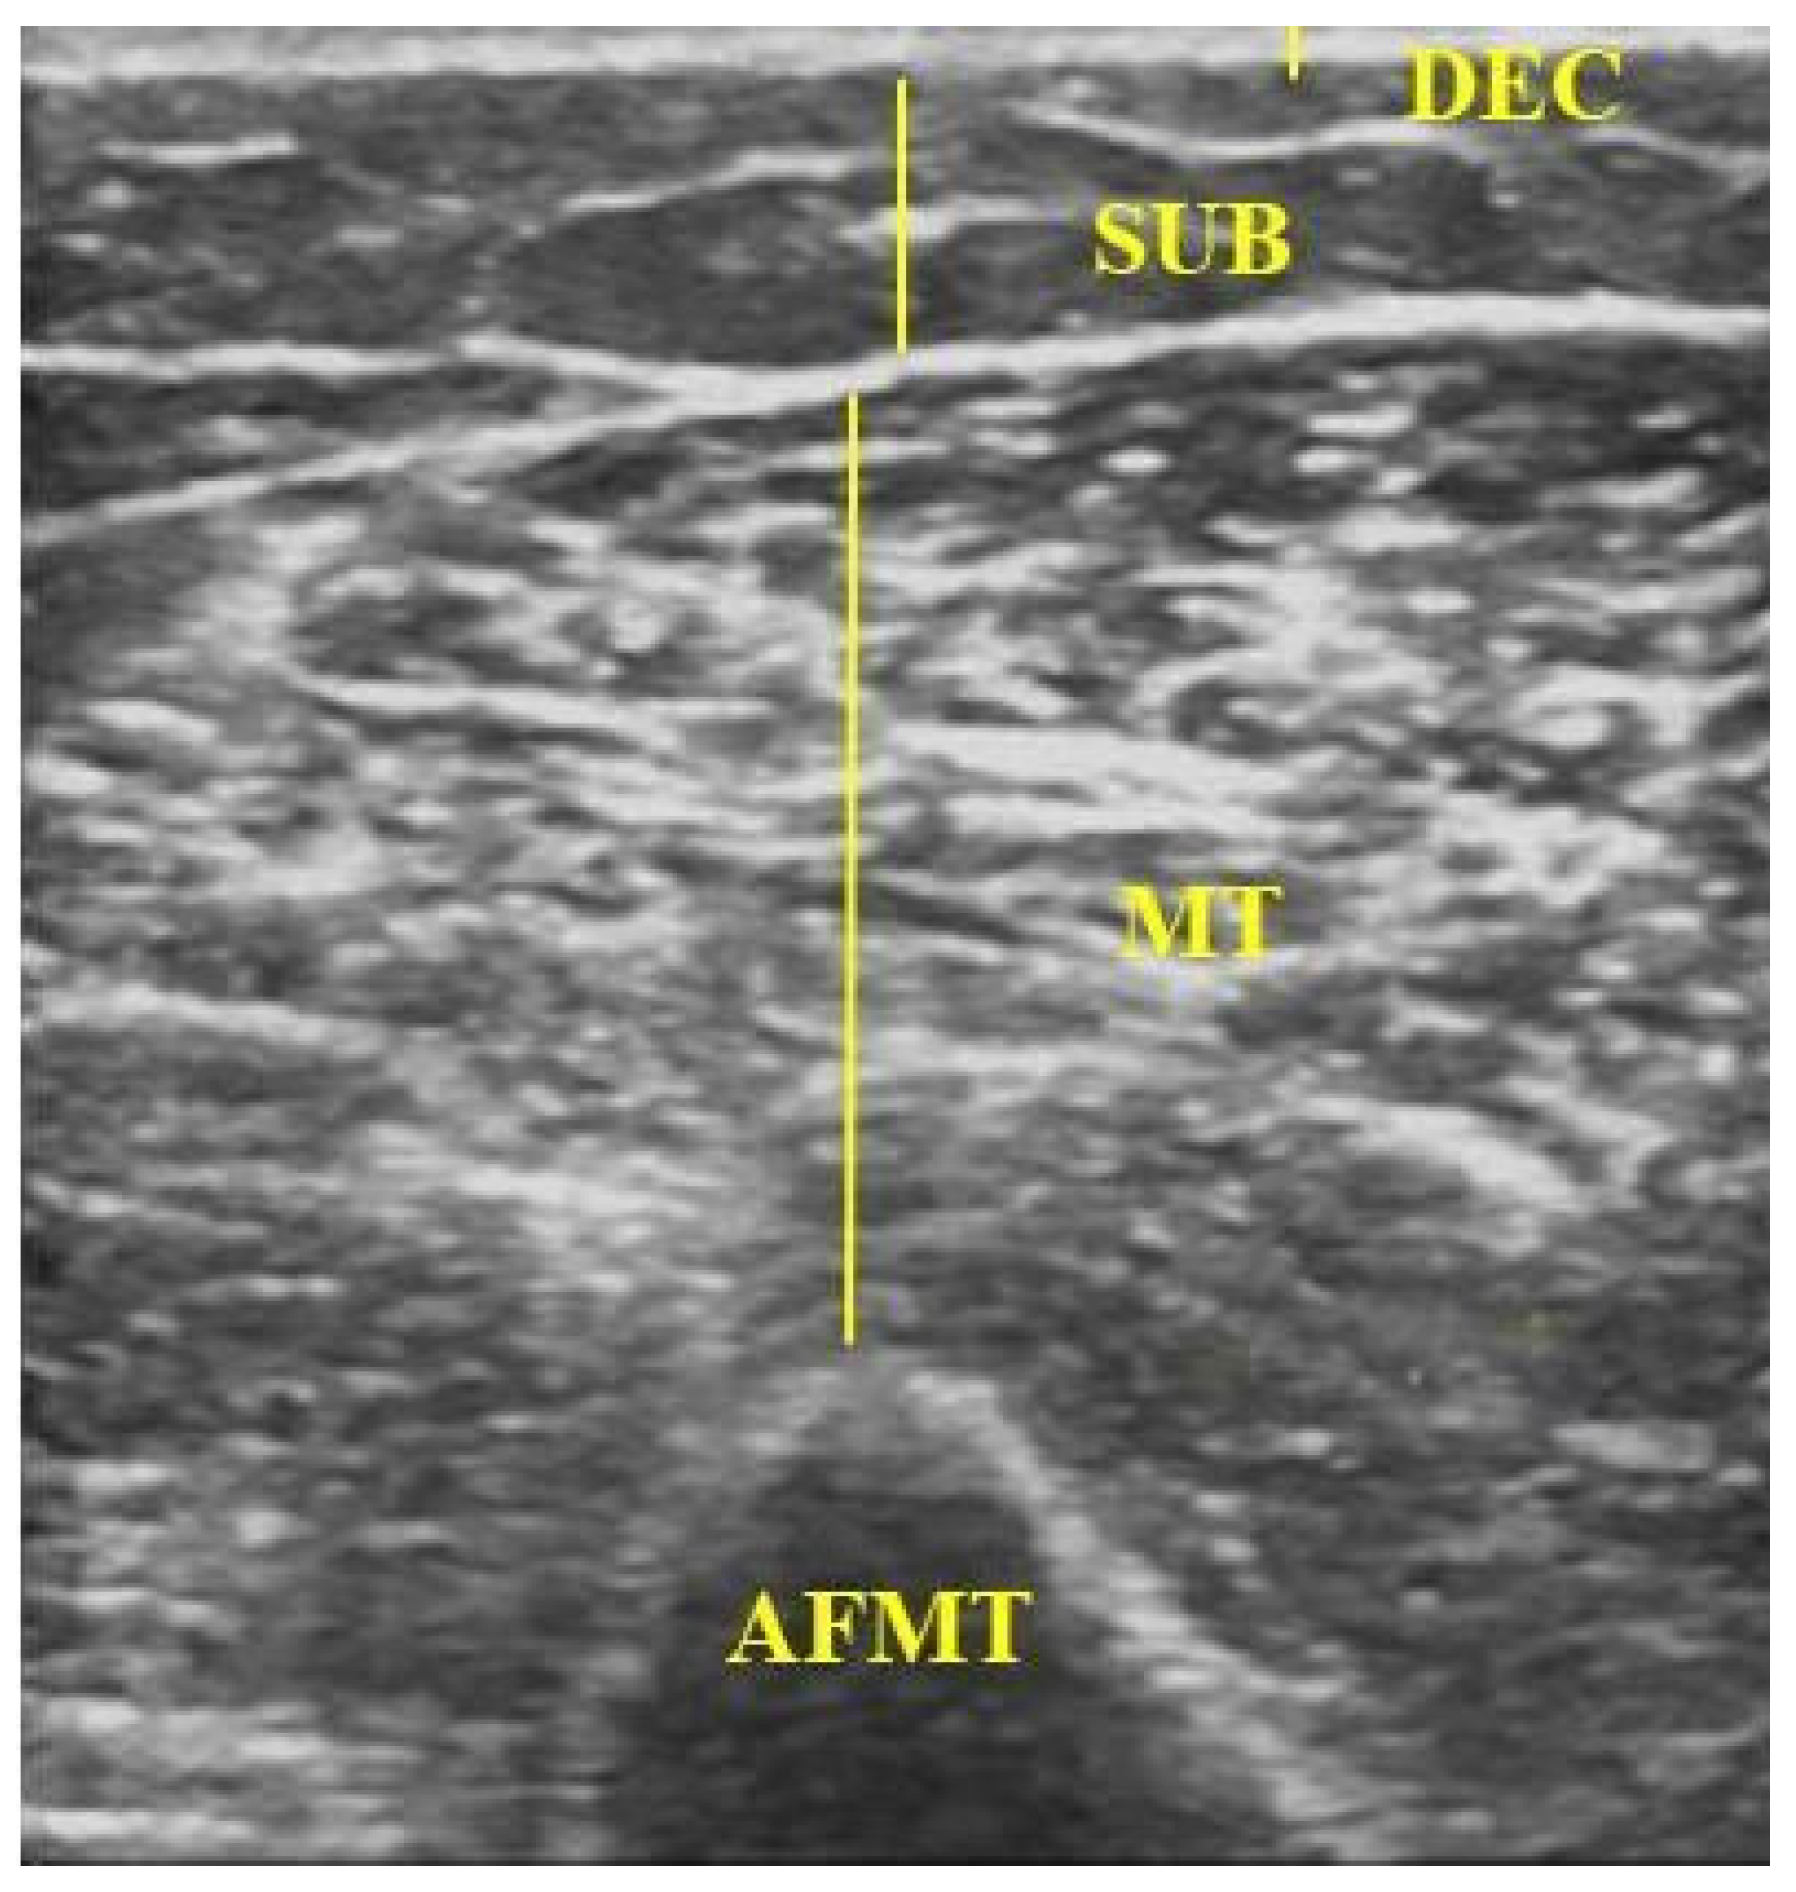

B-mode ultrasound images were acquired using a LOGIC V5 system (GE) with a linear L6-12 transducer. Standardised parameters were used for all measurements: 8 MHz frequency, 79% gain, and 8 cm depth. In each limb, two regions of interest (ROIs) were defined, one on the forearm and one on the arm, both 10 cm from the cubital fossa [23]. Images were captured with the transducer positioned perpendicular to the skin over the muscle belly of interest (Figure 1), applying minimal pressure and using a water-based conductive gel [24]. After freezing the image, the following were measured: (i) the dermal–epidermal complex (DEC)—the linear distance from the posterior echogenic border of the epidermal entry echo to the posterior echogenic border of the dermis [25]; (ii) subcutaneous tissue (SUB)—the distance between the DEC and the muscle fascia [25,26]; (iii) muscle thickness (MT) of the forearm flexors (FMT)—the distance between the radius and the muscle interface [27]; and muscle thickness of the arm flexors (AFMT)—the distance between the muscle interface and the humeral periosteum, including the biceps brachii and brachialis muscles (Figure 2) [28,29].

Figure 2.

Ultrasound image showing measurements of DEC, SUB, and MT of the arm flexor muscles. DEC: dermal–epidermal complex; SUB: subcutaneous tissue; MT: muscle thickness; AFMT: arm flexor muscle thickness. Source: the authors (2025).